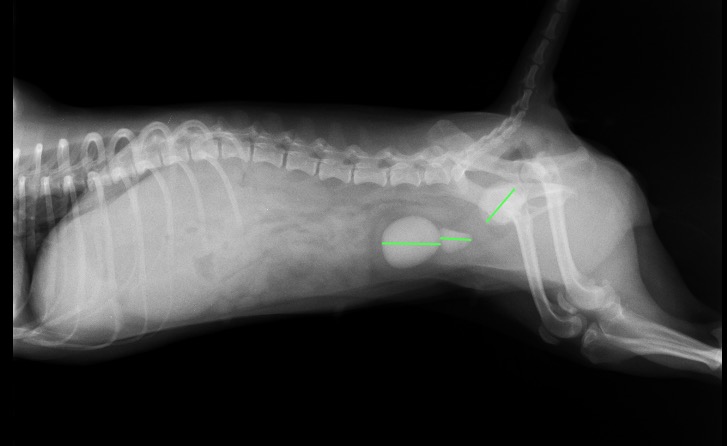

レントゲン検査では膀胱内に、3つのX線不透過性の物体が確認されました。(写真1、2)

写真2